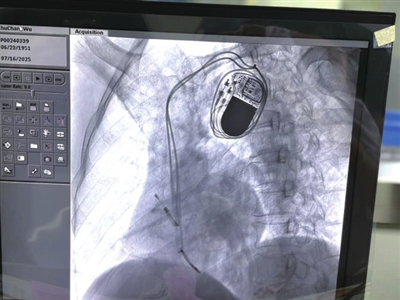

本报讯(记者 叶子 通讯员 陈琳 王芳)近日,市中医医院心病科手术室传来好消息,一名三度房室传导阻滞患者在医护团队的协作下,成功植入心脏起搏器。术后患者心率恢复正常,胸闷、头晕等症状明显缓解。这例手术的成功,标志着该院在心律失常介入治疗领域实现“零的突破”,为中西医结合守护心脏健康打开了新局面。

手术当天,在DSA设备的精准引导下,主刀医师沉稳操作,仅用40分钟就顺利完成了静脉穿刺、电极植入、起搏器调试等关键步骤,全程出血量不足5毫升。术后,科室又采用中药外敷、穴位贴敷等中医护理技术,帮助朱大爷加快伤口愈合,减轻术后不适。